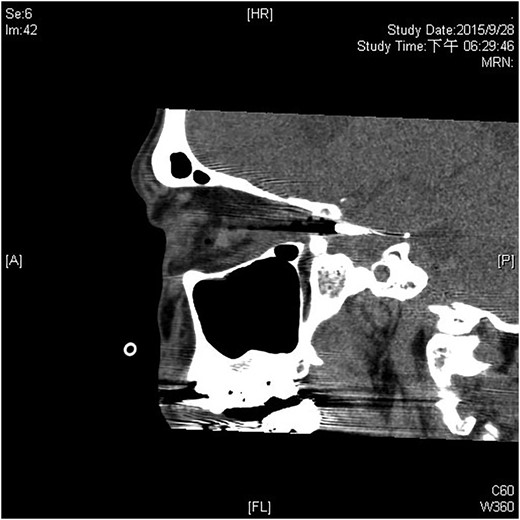

A 60-year-old man was admitted to our medical ward due to aspiration pneumonia. He had a medical history of diabetes mellitus, end-stage renal disease; a tuberculosis bacilli-related thoracic spine infection with paraplegia, and a previous coronary artery bypass graft. During his third day at the hospital, he obtained a ballpoint pen and inserted it into his left eye. On physical examination, the patient appeared to be alert with normal vital signs. The ballpoint pen protruded from his left upper eyelid; it was firmly lodged in his left medial orbit between the globe and nose, causing left eye proptosis (Fig. 1). Neurologic examinations revealed that the patient was neurologically intact except for complete left ophthalmoplegia. Brain CT scanning revealed a tubular foreign body that was located in the anteroposterior plane extending from the orbital apex and directly into the parasellar region (Fig. 2). The metallic portion of the foreign body was entrapped in left optic canal (Fig. 3). There was no evidence of intracranial hemorrhaging or a rupture in the globe (Fig. 4). The patient was treated with high-dose steroids to protect the optic nerve. The plastic ballpoint pen and metallic tip was withdrawn from the orbit smoothly at bedside, and no craniotomy was required. The ballpoint pen had been inserted to an estimated depth of 7 cm through the eyelid and into the orbit. The patient was then transferred to the ICU for close neuro-observation. We initiated intravenous broad-spectrum antimicrobials and vancomycin therapy and continued these medications for three weeks. A psychiatrist was consulted for a complete psychiatric evaluation and suicide prevention. The follow-up CT scan showed no retained foreign bodies or intracranial hemorrhaging (Fig. 5). At the last follow-up examination 2 months after the injury, the patient presented with complete left ophthalmoplegia and blepharoptosis but intact visual function.

The ballpoint pen was firmly lodged in his left medial orbit between the globe and nose.

The ballpoint pen tip reaches into the parasellar region via the optic canal.